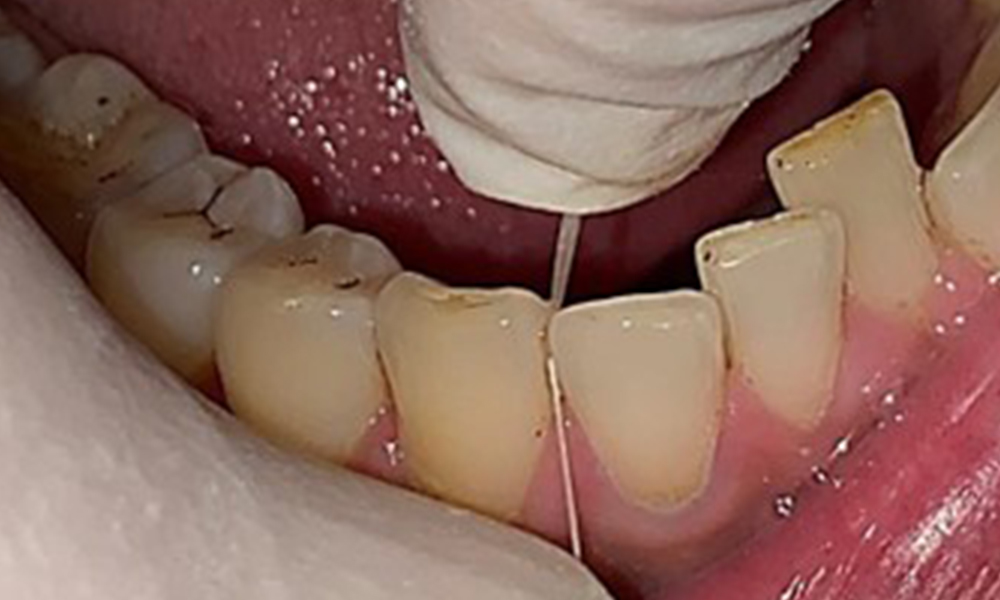

Дентални резултати

Пациентът има пълно съзъбие с общо 28 зъба. Налице са забележими ерозии и атриции. (Фиг. 4, Фиг. 5). Поради бруксизъм пациентът е носил шина с коригиран блок на захапката през нощта в продължение на много години. Ерозиите са причинени от продължителна консумация на изотонични напитки. Не сe наблюдава загуба на пародонтална кост или активни кариозни лезии.

Инструкциите и мотивацията са важни компоненти на тези срещи. Доброто поведение и разбиране на оралната хигиена в домашни условия са важни за пациентите. Натрупването на зъбна плака е особено видимо в цервикалните области (фиг. 8).